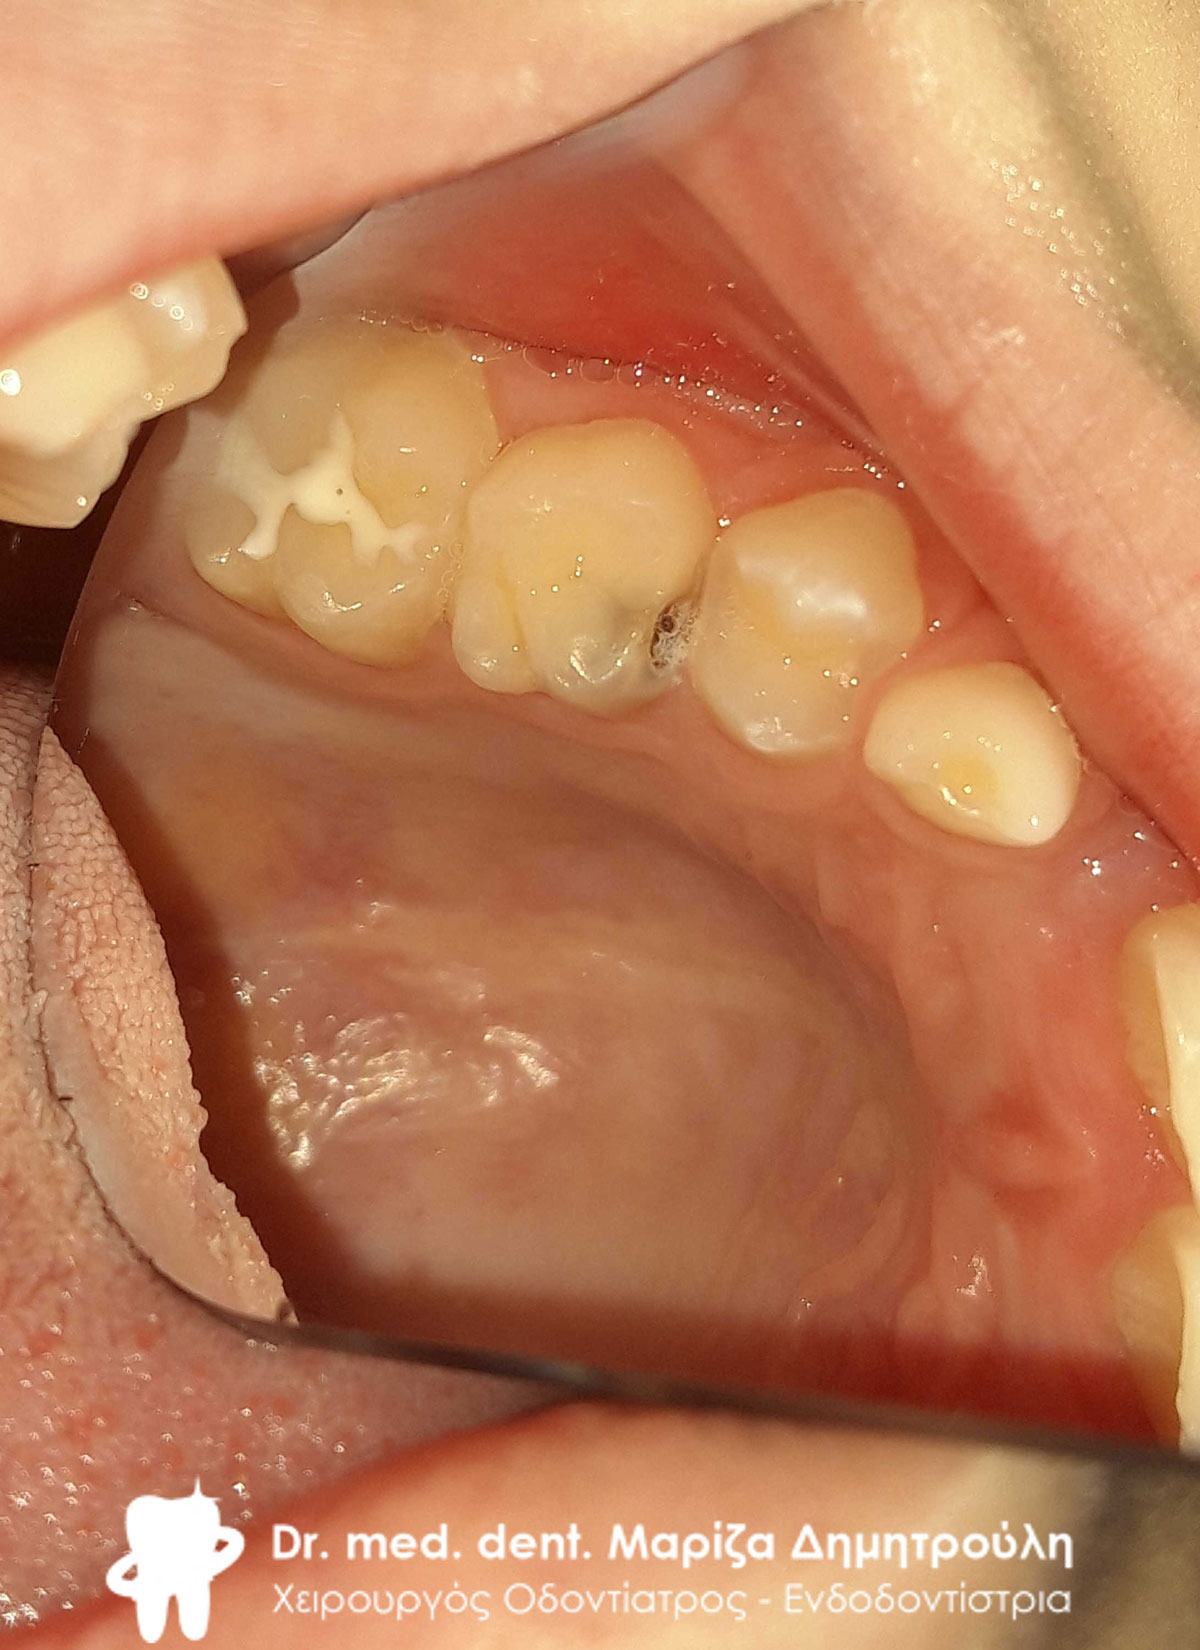

ΠΡΙΝ

ΜΕΤΑ

Κορίτσι ηλικίας 9 ετών αναφέρει οτι πονάει στην πάνω αριστερή πλευρά του στόματος της όταν μασάει. Μετά την κλινική εξέταση διαπιστώθηκε η ύπαρξη 2 τερηδονισμένων δοντιών. Στον πρώτο μόνιμο αριστερό γομφίο είναι εμφανής η ύπαρξη τερηδόνας, της οποίας η έκταση αποδείχτηκε αρκετά βαθιά κατά τη διάνοιξη του δοντιού. Στο δεύτερο νεογιλό (παιδικό) γομφίο παρατηρήθηκε η ύπαρξη τερηδονικής κοιλότητας μεσαίου βάθους.

Μετά την απομάκρυνση της τερηδόνας από τα δύο δοντάκια πραγματοποιήθηκαν λευκά σφραγίσματα σύνθετης ρητίνης.